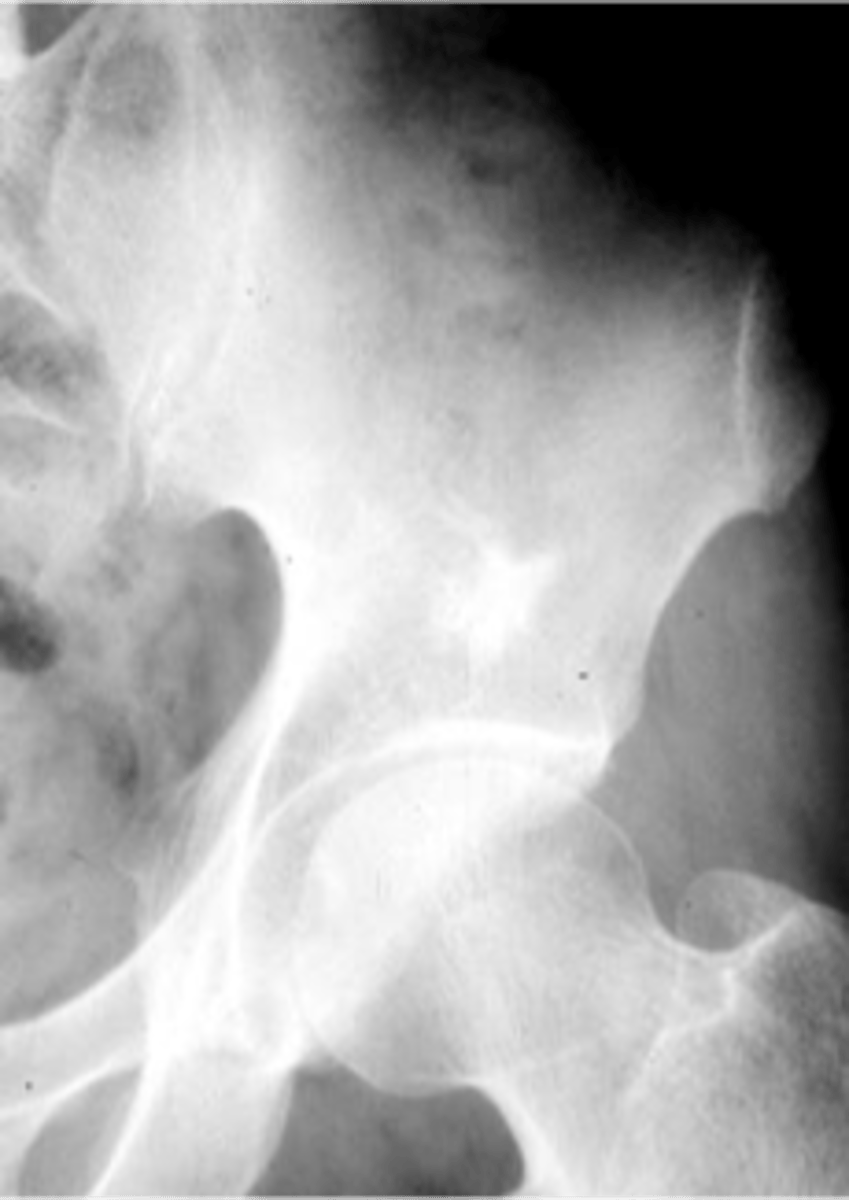

Bone island

- Any age

- Adults > children

- Asymptomatic

- Usually solitary

- Any bone (except skull)

Enostoma/enostosis

Normal tissue in an abnormal area

- Epiphyseal, metaphyseal

- Medullary

- Round/oval

- Radiating border ("brush border")

- Radiodense

- May change size

- May be warm on bone scan

State the radiologic features of a bone island (enostoma/enostosis)

- Ischium

- Ilium

- Sacrum

- Proximal femur

- Humerus

- Vertebra

- Talus

- Scaphoid

State the locations for a bone island

Giant bone islands

ID

- Bone island

- Kidney stone*

22 y.o. male with L/S pain, post motor vehicle accident

- Differential diagnosis?

Osteopoikilosis

Diagnosis?